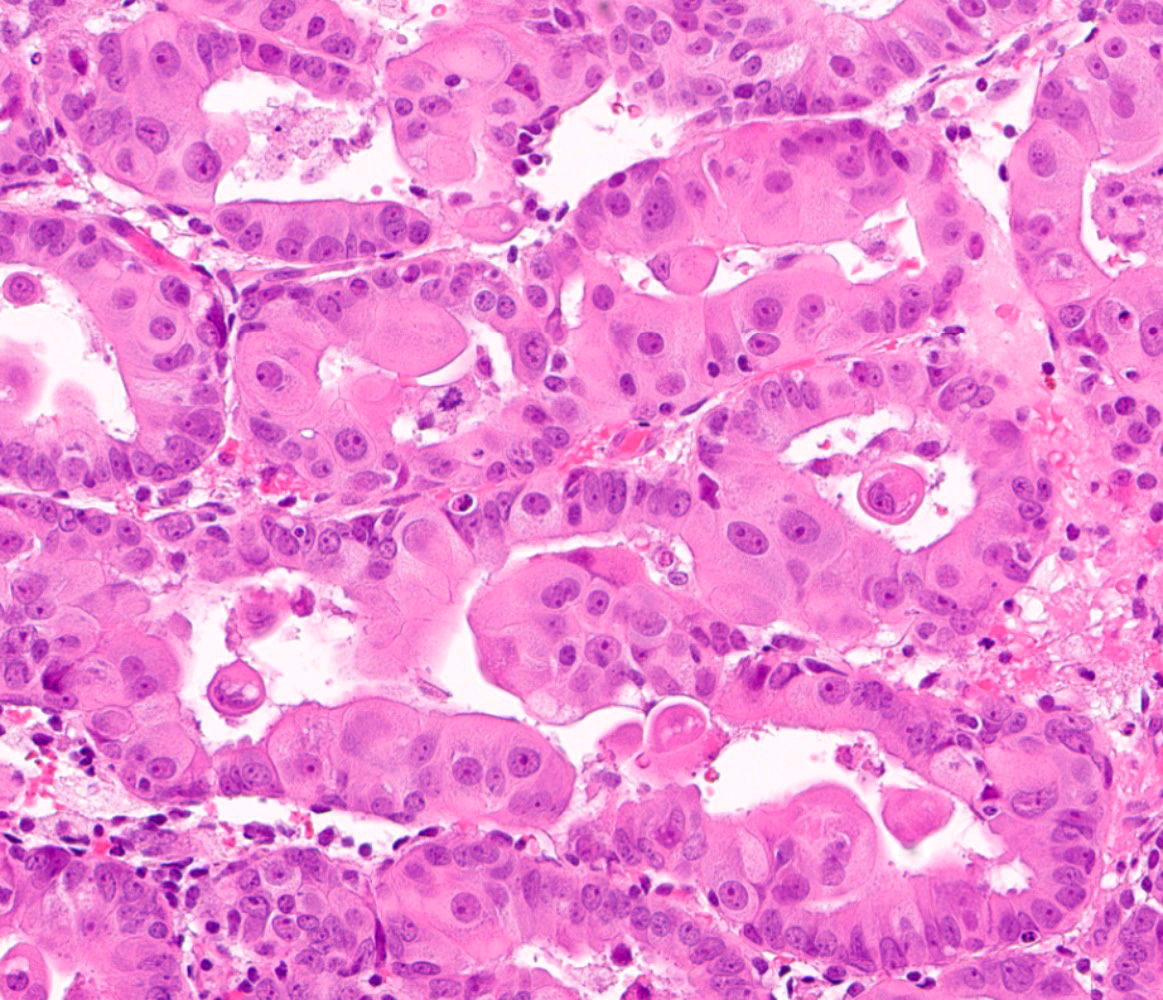

Microscopic (histologic) images

Contributed by Jessica L. Bentz, M.D.

- Mucinous metaplasia (Gynecol Oncol 2015;136:389, Diagn Pathol 2017;12:39):

- Cuboidal to columnar cells, most commonly resembling endocervical epithelium

- Rarely, resembling gastric and intestinal type metaplasia

- Generally cytologically bland

- Subtypes (Mod Pathol 1999;12:1137):

- Type A: single cell layer lining the epithelial surface, with or without glandular involvement

- Type B: focal / patchy papillary / micropapillary changes

- Type C: extensive papillary, cribriform or microacinar architecture

- Mucinous metaplasia may be found in the ovaries or cervix of patients with endometrial mucinous metaplasia

- Cuboidal to columnar cells, most commonly resembling endocervical epithelium

- Papillary metaplasia (Am J Surg Pathol 2013;37:167):

- Subtypes:

- Papillary syncytial: pseudostratified eosinophilic cells with indistinct cell borders and loss of nuclear polarity (Int J Gynecol Pathol 2012;31:206)

- Sometimes termed as pseudopapillary due to the absence of fibrovascular cores

- Generally located on the surface

- Associated with stromal breakdown

- Papillary proliferations: true papillae with fibrovascular cores (Am J Surg Pathol 2001;25:1347)

- Simple / localized: short, nonbranching

- Complex / diffuse: numerous branching with papillae and micropapillae

- Analogous to endometrial intraepithelial neoplasia / atypical hyperplasia